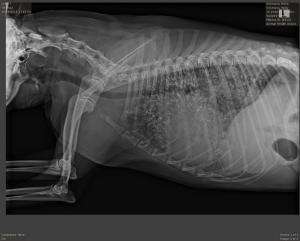

These are rads from a 14 year old Mini Aussie who presented for acute (per owner) onset of cough and respiratory difficulty. She was tachypneic, cyanotic, and had harsh lung sounds and a III/VI murmur. She was not febrile. She did cough up some foamy blood tinged froth.

Is it possible t hat this is CHF in a dog with chronic lung pathology? I have doubts that this dog had no respiratory symptoms prior to this episode, but don’t know as she hadn’t been to a vet since she was a puppy.

Cardiomegaly here and diffuse

Cardiomegaly here and diffuse alveolar pattern. Id be concerned for metstatic lung disease and maybe pericardial effusion. The lung pattern isnt typical of CHF and wet lung as that starts tapering from the caudal medistainum and the lung vasculature doesnt support that. Let me see if Dr. Ondreka can comment.

Echocardiogram and abdominal ultrasound is what i woud do next looking for primary badness.

we were thinking this might be neoplastic. The mineralization makes it difficult to read. Poor little dog! jas

Other possiblites would be

Other possiblites would be fungal disease and anthracosis.

Thoracic wall ultrasound

Thoracic wall ultrasound could be useful to get a sample for metastatic disease